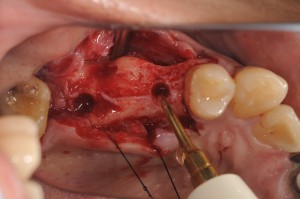

このケースは、上顎5,7番部位へ2本のストローマンティッシュレベルインプラントをソケットリフトで埋入しました。

5番部位の洞底の皮質骨が固くオステオトームのみでは、若木骨折できなかったので、ピエゾサージェリーを用いました。

7番部位は、スムーズにオステオトームテクニックでソケットリフトできました。